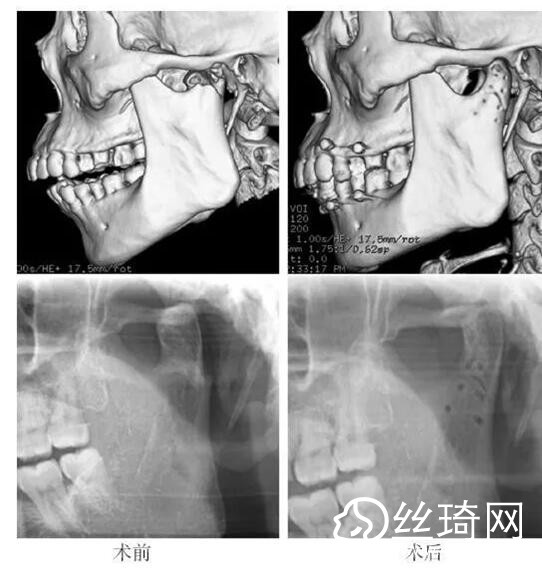

在106側(cè)中,髁突高位矢狀骨折46側(cè),中位髁頸骨折26側(cè),低位髁頸下骨折34側(cè)。髁突高位矢狀骨折及中位髁頸骨折均經(jīng)耳屏前徑路復(fù)位;34側(cè)低位髁頸下骨折中,經(jīng)耳屏前徑路復(fù)位13側(cè),頜下徑路復(fù)位19側(cè),頜后徑路復(fù)位1側(cè),穿腮腺?gòu)铰窂?fù)位1側(cè)。髁突高位矢狀骨折復(fù)位后以1~2枚可吸收長(zhǎng)螺釘固定(圖1)[3],采用的可吸收內(nèi)固定系統(tǒng)為BioSorb(ConMed Linvatec,芬蘭)、Inion OTPS(Inion,芬蘭);規(guī)格:直徑2 mm,長(zhǎng)度15~20 mm。中位髁頸骨折及低位髁頸下骨折多以2塊可吸收板固定(圖2)[3],個(gè)別病例以1塊或3塊可吸收板固定,采用的可吸收內(nèi)固定系統(tǒng)為BioSorb(ConMed Linvatec,芬蘭)、Grand Fix(Gunze,日本)、Inion OTPS(Inion,芬蘭);規(guī)格:直4孔板,孔徑 mm或2.5 mm,長(zhǎng)度21~35 mm,螺釘直徑 mm或2.5 mm,長(zhǎng)度7~10 mm??晌蔗敯宓氖中g(shù)操作采用專用器械工具盒,并遵照廠家操作指引進(jìn)行。

82例髁突骨折患者,術(shù)后隨訪6個(gè)月至3年,平均年。所有患者術(shù)后未訴明X不適,面型基本對(duì)稱,面部肌肉運(yùn)動(dòng)正常,咬合對(duì)位良好,開口度~4.2 cm,平均(±)cm。3例患者開口型輕度偏斜,均為髁突高位骨折,其中2例為粉碎性骨折行骨折碎片摘除,1例為矢狀骨折,以可吸收螺釘固定后,創(chuàng)口感染,隨后行局部清創(chuàng)并取出髁突骨折片及可吸收螺釘,創(chuàng)口愈合良好。96側(cè)髁突骨折中,2例髁頸下骨折術(shù)后復(fù)查CT顯示輕度移位,但患者無(wú)功能障礙,持續(xù)觀察,未做特殊處理。其他患者未見明X排斥反應(yīng)及并發(fā)癥。

本組病例中,絕大多數(shù)髁頸、髁頸下骨折均經(jīng)耳屏前或頜下切口進(jìn)行復(fù)位固定,均獲得了良好的復(fù)位固定性及療。有2例患者輕度移位,可能與過(guò)早承重及可吸收材料的強(qiáng)度較弱有關(guān)。